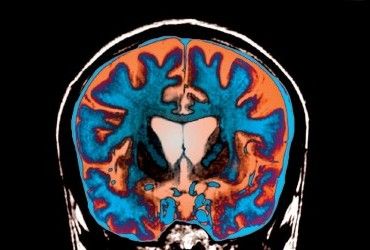

У США вчені вперше виявили, як одні ліки можуть поліпшити виживання при пухлинах головного мозку у молоді та дітей.

Як пише видання Newsweek, пухлина, відома як дифузна серединна гліома, є особливо агресивною формою раку, яка зазвичай зустрічається у молоді чи дітей. Коли цей рак також має мутацію H3K27M, лікування стає ще складнішим. Середнє виживання людини з цим типом пухлини становить від 11 до 15 місяців. Вчені тестували препарат на 71 пацієнті з дифузними гліомами з мутацією H3K27M. Всі учасники приймали препарат ONC201. Дослідники виявили, що третина з них прожила більше двох років. Середнє виживання серед усіх пацієнтів становило 22 місяці.

В даний час цей тип раку лікується радіацією, але це не простий метод, оскільки пухлина знаходиться в критичному відділі мозку. Але зараз дослідники виявили, що препарат під назвою ONC201 майже вдвічі збільшив тривалість життя пацієнтів з пухлиною порівняно з тими, хто не приймав препарат.

ONC201 - це експериментальний препарат, який вибірково вбиває ракові клітини. Вчені знали про ефективність препарату в боротьбі з цим видом раку, але нове дослідження показало, наскільки він збільшує тривалість життя. Це означає, що препарат може бути ефективним методом лікування цього поки що невиліковного раку.